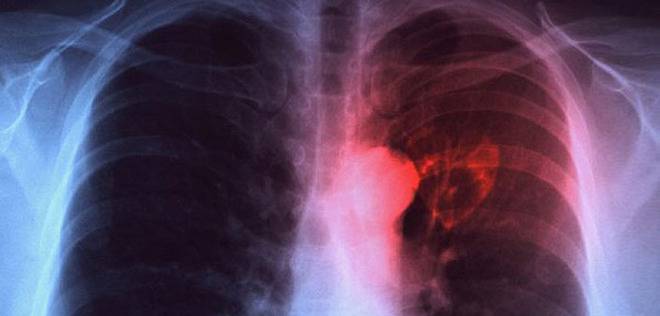

Туберкулозата е хронично инфекциозно заболяване, което в 90 % от случаите засяга белодробната система, а в 10% – и други органи и системи (централна нервна система, сърце, очи, кожа, органи на коремната кухина, кости и стави, уро-генитална система и други).

Причинителят на туберкулозата е Микобактериум туберкулозис (бактерий на Кох), който се отличава със значителна устойчивост във външната среда. Повечето от хората, които се заразяват с туберкулозните бактерии, успяват да се «преборят» с тях и да спрат растежа им – бактериите остават да живеят в тялото на заразения човек, но не са активни. След време може да се активират от само себе си. Това състояние се нарича скрита туберкулозна инфекция – хората със скрита инфекция нямат определените за заболяването симптоми и не могат да заразяват други хора.

Източници на зараза могат да бъдат болните от туберкулоза хора и животни (главно едър рогат добитък, по-рядко свине, птици и други), както и техните продукти.Проникването на инфекцията най-често става през дихателните пътища. При кашлица, кихане, разговор болният отделя туберкулозните бактерии във въздуха. От пръските при кашляне и храчене хората, които се намират в близост, могат да се заразят непосредствено по въздушно-капков път. В храчките на болните се съдържат милиони бактерии. Заразата може да се пренeсе и чрез праха в стаите и по улиците, където туберкулозните бактерии остават дълго време жизнеспособни.

СИМПТОМИ НА БЕЛОДРОБНАТА ФОРМА НА ЗАБОЛЯВАНЕТО

► Кашлица, която може да продължи седмици, като в началото се наблюдава леко покашляне, а при напредване на болестния процес кашлицата се засилва и става влажна;

► Храчене – болните отделят храчки главно сутрин, понякога примесени с кръв;

► Повишена температура – болните имат повишена температура за продължителен период от време (дори с месеци). Възможно е заболяването да протече и без повишена температура;

► Изпотяване – то е обилно, особено нощно време;

► Болки в гръдния кош – те се срещат при повечето болни между плешките, в раменните и страничните области на гръдния кош, като се засилват при дишане и кашлица;

► Безапетитие – то води до намаляване на телесното тегло;

► Задух – този признак е характерен за напредналите стадии на болестта;

► Отпадналост и безсилие – тези симптоми продължават дълго време.

Туберкулозата може да протече и напълно безсимптомно в около 15% от случаите. При възрастни хора често наподобява пневмония или друго инфекциозно заболяване.